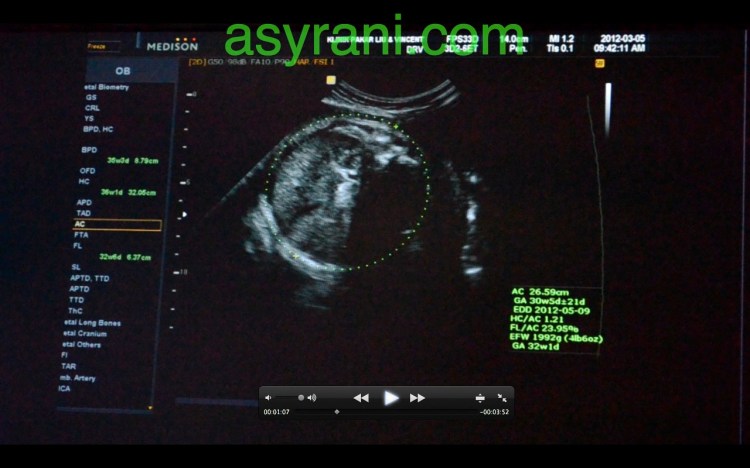

Gambar ini untuk ketika mengukur lilitan abdomen (waist)

Bacaan yang diperoleh setelah mengukur